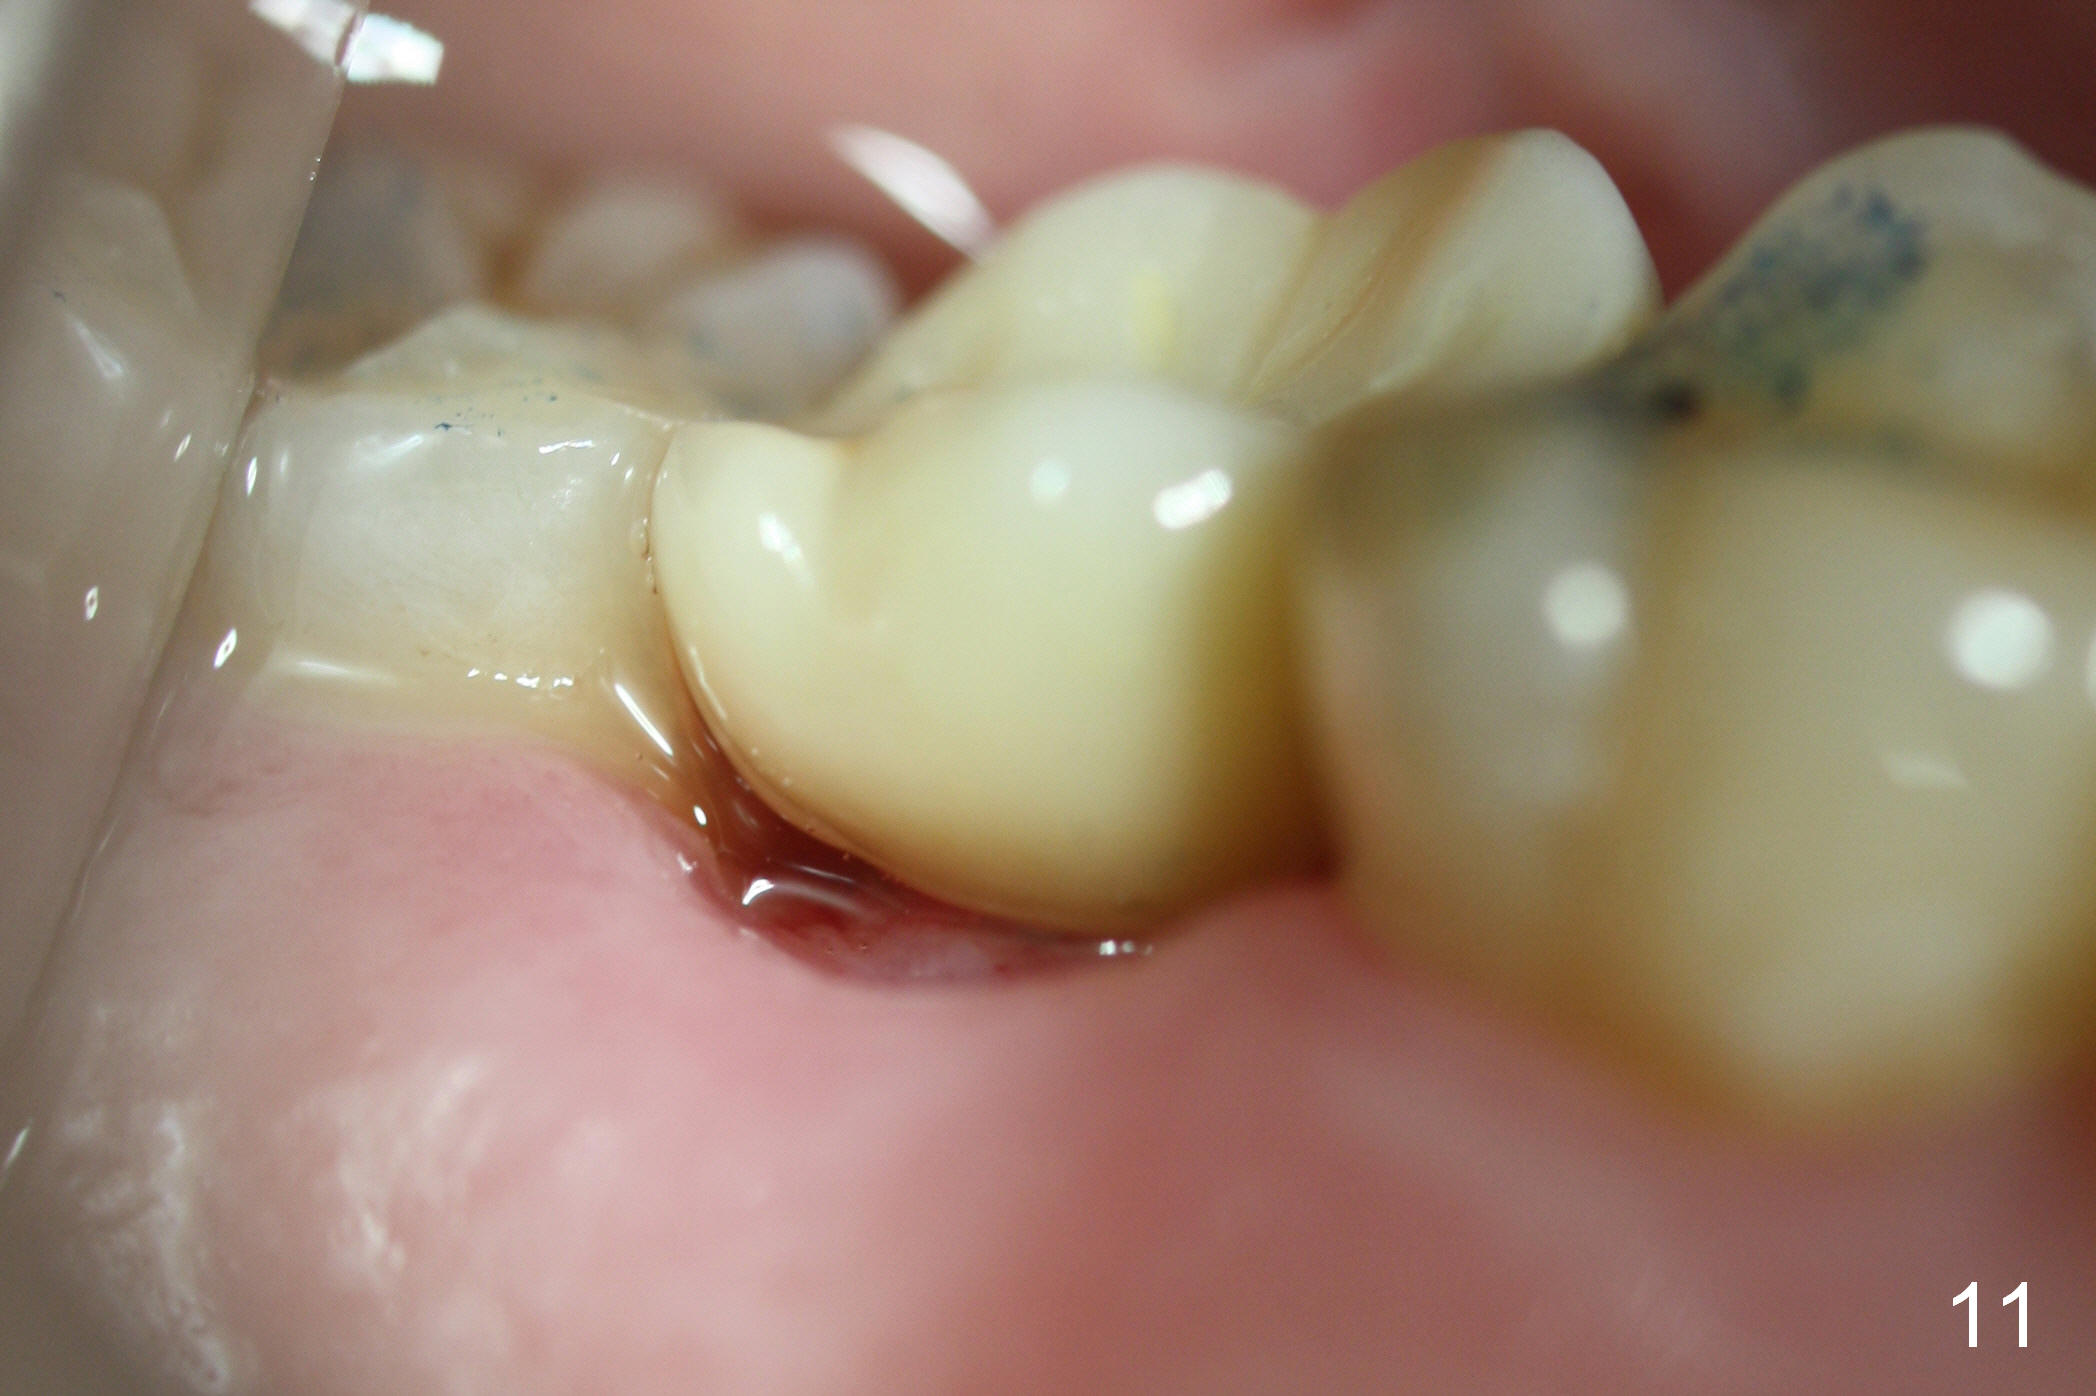

The implant remains stable 2.5 months postop without abnormal bone resorption (Fig.9). Since the provisional has dislodged on several occasions, impression is taken for final restoration. When the provisional is removed 3 months postop, the margin of the restoration is shown to be subgingival (Fig.10 arrowheads), but is distinctly separated from the gingiva. This is due to the presence of the provisional (its margin were fabricated slightly deeper). The provisional is also intentionally fabricated slightly larger than the final restoration. When the latter is cemented, there is space to remove extra cement trapped subgingivally (Fig.11). No cement is visible post cementation (Fig.12 (C: crown)). Eighteen months post cementation, the patient returns for recementation. After laser gingivectomy and Panavia resin bonding, PA shows residual cement (Fig.13 ^). After repeated removal with Piezo scaler and explorer, the residual cement appears to be smaller, which is ignored at the time of X-ray taking (Fig.14 ^). More dismayed is tight mesial contact. Water pik is recommended. When peri-implantitis develops later on, make an incision for cement removal. If the crown is dislodged soon, check whether the existing abutment is loose, remove acrylic in the access hole and remove the abutment. Install a new 4x3 mm one. Trim the abutment carefully and more on the opposing tooth.